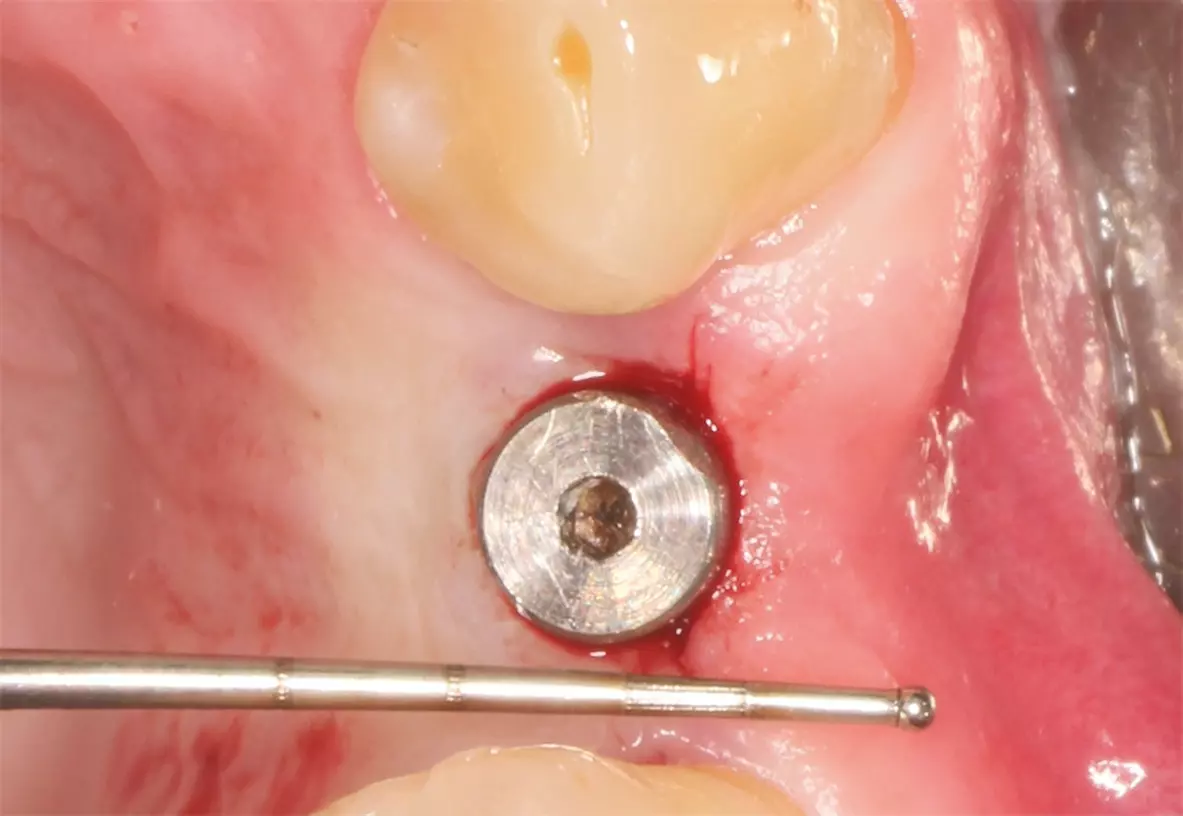

Nach ausführlicher Aufklärung und Beratung wurde die Extraktion des Zahnes 24 geplant. Zu diesem Zeitpunkt entschied sich der Patient gegen eine präventive Maßnahme zur Versorgung der Extraktionsalveole. Eine schonende Extraktion des Zahnes erfolgte komplikationslos unter gängiger Lokalanästhesie. Dabei konnte die vestibuläre Lamelle regelrecht erhalten werden (Abb. 2). Die Extraktionsalveole wurde mit einer Naht versorgt (Abb. 3). Ein Tag nach der Extraktion zeigt sich eine fibrinbelegte Wunde mit zeitgerechter und regelrechter Wundheilungsstatus (Abb. 4). Nach einer Woche wurde die Naht entfernt. Es zeigte sich zu diesem Zeitpunkt weiterhin eine fibrinbelegte Wunde mit einer okklusalen Mulde, die etwa 5 mm tief ist. Die Heilung war nach einer Woche also noch nicht komplett abgeschlossen (Abb. 5). In der frühen Wundheilungsphase berichtete der Patient beschwerdefrei gewesen zu sein. Drei Monate später stellte sich der Patient erneut vor mit dem Wunsch einen festsitzenden Zahnersatz zu bekommen. Die Extraktionsalveole zeigte eine vollständige Wundheilung und eine deutliche vestibuläre Knochenresorption (Abb. 6). Das Implantat konnte trotzdem eingesetzt werden und zeigt zum Zeitpunkt der Implantation eine adäquate Primärstabilität (Abb. 7). Nach drei Monaten wurde das Implantat freigelegt (Abb. 8) und anschließend mit einer Krone versorgt (Abb. 9).